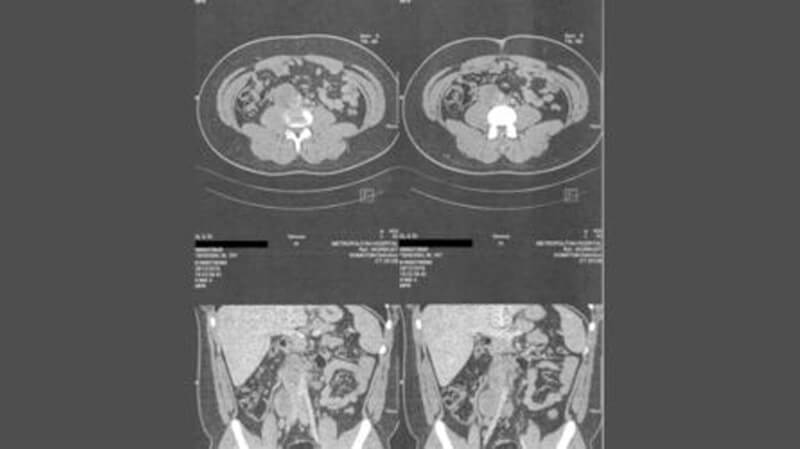

Η κλινική εξέταση που ακολούθησε, ο υπερηχογραφικός έλεγχος του οσχέου, η αξονική τομογραφία θώρακος και κοιλίας (άνω και κάτω) ανέδειξαν έναν ευμεγέθη όγκο δεξιού όρχεος, 9 εκατοστά περίπου σε διάμετρο, με πολλαπλά παθολογικά διογκωμένους λεμφαδένες στον παρααορτικό χώρο, κυρίως επί τα δεξιά της μέσης γραμμής που συρρέανε και σχημάτιζαν block, ο μεγαλύτερο ορατός με διαστάσεις 4,5Χ3,5 εκατοστά.

Κατόπιν εισηγήσεως του οικογενειακού Ιατρού του ασθενούς, ο νεαρός ασθενής παραπέμφθηκε στην Ογκολογική Κλινική του Δρ. Χριστοδούλου Χρήστου, του Νοσοκομείου Metropolitan, για άμεση χημειοθεραπεία. Μετά από τέσσερεις κύκλους του ενδεδειγμένου σχήματος χημειοθεραπείας η ανταπόκριση ήταν ικανοποιητική αλλά όχι πλήρης. Οι αξονικές τομογραφίες κοιλίας στο ενδιάμεσο (17/02/2020) και στο τέλος της χημειοθεραπείας (02/04/2020) έδειξαν μία σταδιακή απεικονιστική βελτίωση σε σύγκριση με τον προγχειρητικό έλεγχο με μείωση της διάστασης των απεικονιζόμενων λεμφαδένων παραορτικά και κατά μήκος των λαγονίων αγγείων. Επανελεγχόταν όμως λεμφαδένας στο επίπεδο διχασμού της κοιλιακής αορτής με σταδιακή μείωση των διαστάσεων του, στην εξέταση στις 02/04/2020 με 2,4 εκατοστά μέγιστη διάμετρο έναντι 2,6 εκατοστά στις 17/02/2020, από 4,5 εκατοστά που ήταν προεγχειρητικά.

Παρακάτω βλέπετε την σειρά των αξονικών τομογραφιών του ασθενούς αρχικά πριν το ρομποτικό χειρουργείο (29/12/2019), στην μέση της χημειοθεραπείας (17/2/2020), στο τέλος της χημειοθεραπείας (2/4/2020) με τον μεγάλο υπολειπόμενο λεμφαδενικό όγκο οπισθοπεριτοναϊκά και την μαγνητική τομογραφία κοιλίας με πολυπαραμετρική μελέτη ένα περίπου μήνα μετά την ρομποτική οπισθοπεριτοναϊκή λεμφαδενεκτομή διάσωσης (29/5/2020) όπου δεν κανένας λεμφαδένας οπισθοπεριτοναϊκά παρά μόνο μία μικρή κυστική συλλογή υγρού (διαμέτρου 1 εκατοστού), δίκην μη σημαντικής, υποσημαινόμενης λεμφοκήλης.